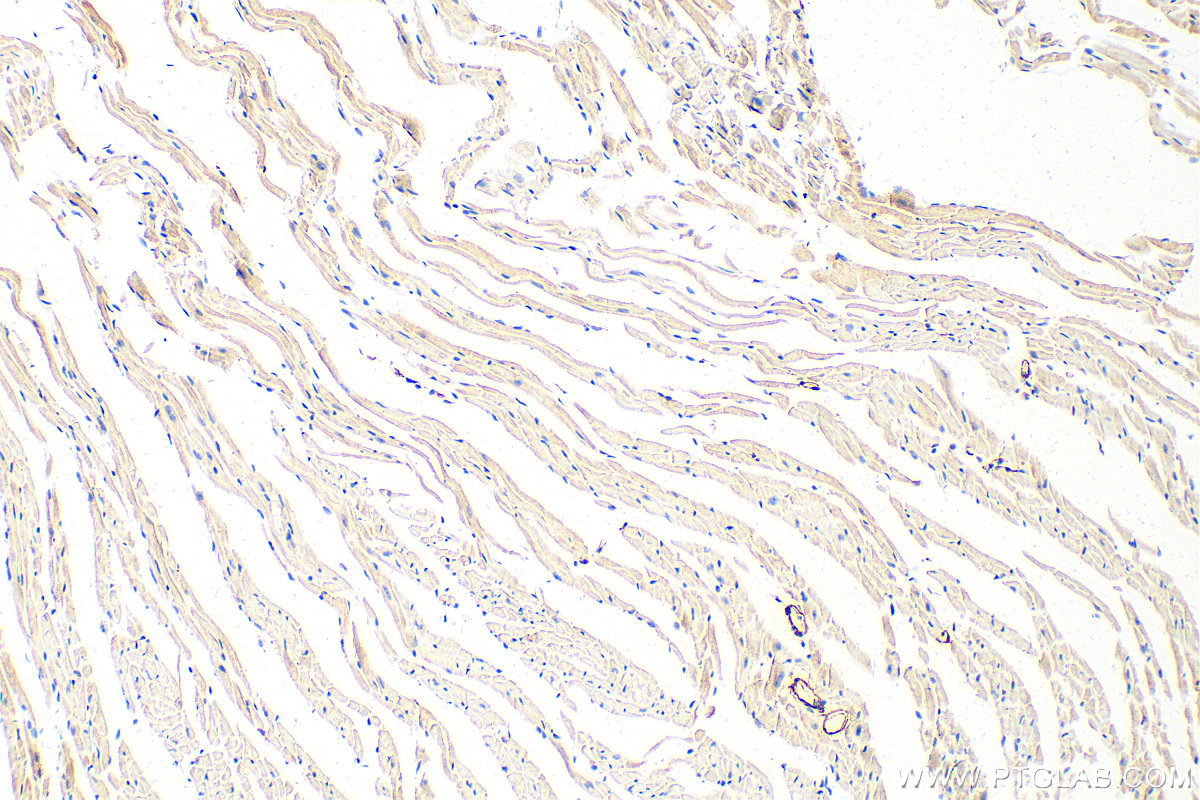

| Positive IHC detected in | mouse heart tissue, human colon cancer tissue, mouse brain tissue Note: suggested antigen retrieval with TE buffer pH 9.0; (*) Alternatively, antigen retrieval may be performed with citrate buffer pH 6.0 |

The transgelin family is a protein group belonging to the 22kd actin-related calponin superfamily. Of all three isoforms, transgelin 1 is the best characterized. Transgelin 1, or SM22alpha, is a specific marker for differentiated smooth muscle cells. Transgelin 2, also known as SM22 beta, is expressed by both smooth and non-smooth muscle cells in a temporally and spatially regulated pattern. Trangenlin 3, also known as NP25, is only found in highly differentiated neuronal cells. This antibody was generated against full-length transgelin 1 protein. It can cross-react with other two transgenes based on the sequence similarity.